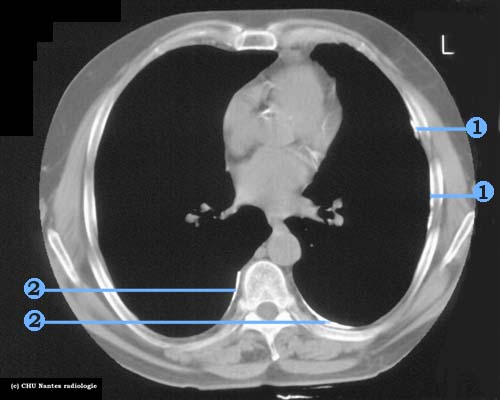

Calcifications pleurales (A)

coupe TDM en fenêtre médiastinale

1 .Calcifications pleurales de la région axillaire gauche

2 . Calcifications pleurales postérieures bilatérales